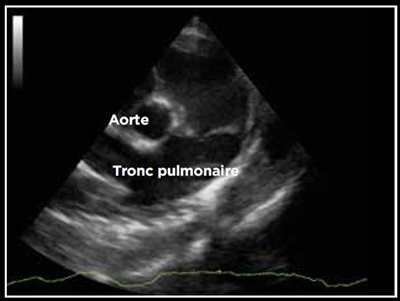

Photo 2 - Persistance du canal artériel, mode Doppler couleur sur une vue crâniale par abord parasternal gauche.

Le canal artériel est visualisé dans 96 % des cas en mode bidimensionnel ou en mode Doppler couleur sur une coupe petit axe transaortique par abord parasternal droit (Photo 1), sur une coupe petit axe par abord parasternal crânial gauche (Photo 2), ou plus facilement sur une coupe longitudinale des gros vaisseaux (aorte et tronc pulmonaire) par abord parasternal crânial et dorsal gauche (Photo 3).